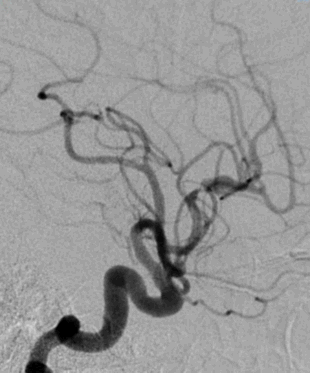

DSA:

长鞘+125cm Tethys®中间导引导管+2m 0.014inch导丝+微导管。

微导管顺利进入大脑前动脉。

125cm Tethys®中间导引导管顺利过眼动脉弯。

微导管造影明确闭塞血管情况。

微导管到达远端。

释放3×20mm取栓支架。

支架锚定后,Tethys®中间导引导管顺利进入大脑前动脉。

继续跟进Tethys®中间导引导管。

抽拉结合。

血流恢复。

观察血流。

3D造影,弹性回缩明显。

引入2.5×20mm支架并释放。

支架植入术后。

血管维持可。